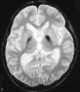

Pantothenate kinase-associated neurodegeneration (PKAN), formerly called Hallervorden–Spatz syndrome, is a genetic degenerative disease of the brain that can lead to parkinsonism, dystonia, dementia, and ultimately death. Neurodegeneration in PKAN is accompanied by an excess of iron that progressively builds up in the brain. [Source: Wikipedia